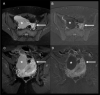

The cause of pelvic pain remains a significant diagnostic challenge, even for experienced radiologists. An accurate differential diagnosis has to be done according to the patient's age and gender. Spontaneous round ligament hematoma is an uncommon cause of acute pelvic pain in adult female patients. To the best of our knowledge, it has never been reported in the literature in the paediatric population. Ultrasound examination is the first line imaging modality for pelvic pain evaluation in young women but it might result inconclusive. Thanks to its panoramic view and multiparametric approach, the MRI can play a pivotal role in the diagnosis of spontaneous round ligament hematoma in paediatric female patients, resulting in a more effective patient's therapeutic management.